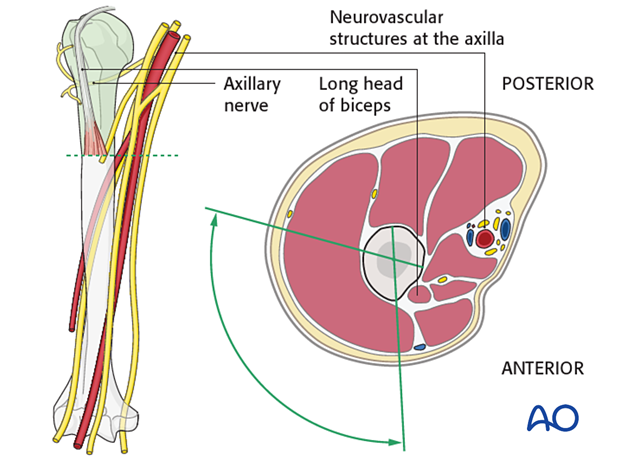

Neurological Structures

Several critical neurological structures are at risk during proximal humerus surgery. The axillary nerve is perhaps the most vulnerable, traversing posteriorly and inferiorly around the surgical neck of the humerus, approximately 5-7 cm distal to the acromion. It innervates the deltoid and teres minor muscles. The musculocutaneous nerve can be at risk with anterior approaches, particularly if dissection extends too far medially, supplying the coracobrachialis, biceps brachii, and brachialis. The radial nerve is located more distally but must be considered, especially with extensive humeral shaft exposure. Awareness of these "safe zones" for screw insertion and surgical dissection is paramount.